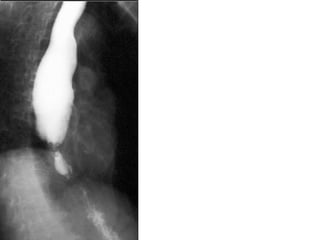

Esophageal scleroderma

Location:

Lower 2/3 (contain smooth muscles).

Pathology:

Smooth muscle atrophy.

Motility disorder:

Decreased peristalsis.

Reflux.

Radiological:

• Dilatation of the lower 2/3 of the esophagus.

• Patulous gastro-esophageal junction.

• Loss of longitudinal folds.

• Esophageal candidiasis.